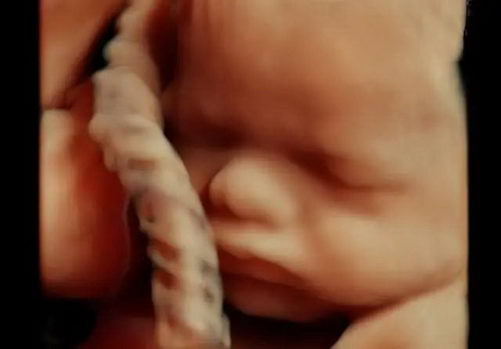

相较普通四维彩超,金标版E10的高清画质堪比MAX电影大片!虽然过去的四维彩超也能看到宝宝吐舌头、吃手指,但常常看到胎宝宝就像个“小泥人”,只能看看大致轮廓;

但金标版E10四维彩超就不同了,您可以实现和宝宝超高清“隔空对视”,亲眼目睹他们的一举一动和乖巧秀容,包括:皱眉、微笑、打哈吸吮和吞咽、小腿交叉盘坐等,提前享受为人母的喜悦。